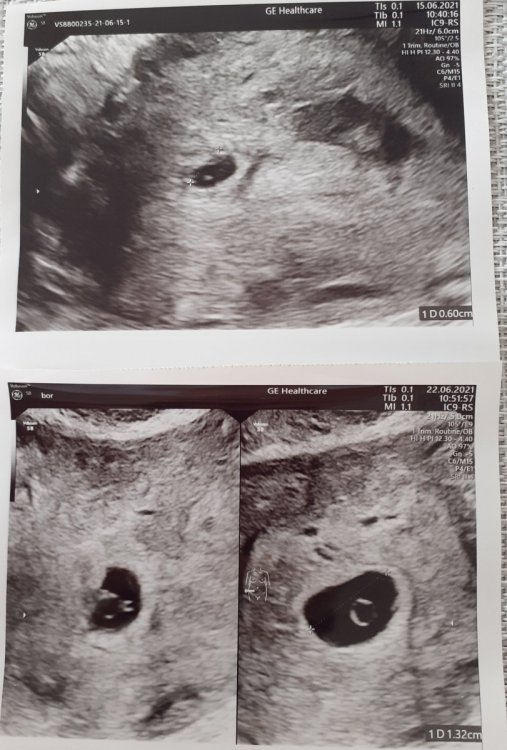

U mnie w pierwszej ciąży w 7tc5d był taki obraz usg. Ciałko żółte za duże w stosunku do pęcherzyka. A u Ciebie zupełnie inaczej to wygląda.

Screenshot_2021-06-22-14-39-50-169_com.miui.gallery.jpg

U mnie twierdzi że za mało urosło od poprzedniego tygodnia. Nie wiem może ja  się nie znam ale na  moje to urosło. Nie wiem czy konsultować to z innym lekarzem czy czekać na bete czy co robić.

Wyszłam. Krwiaki się wchlonely, nie ma śladu. Ale nie podoba mu się jak rosnie zarodek. Mówi że powinien być większy. Jutro mam iść na bete i cały pakiet tarczycy bo mówi że Hashimoto pewnie robi bałagan. Mówił o encortonie. W poniedziałek kolejna wizyta.